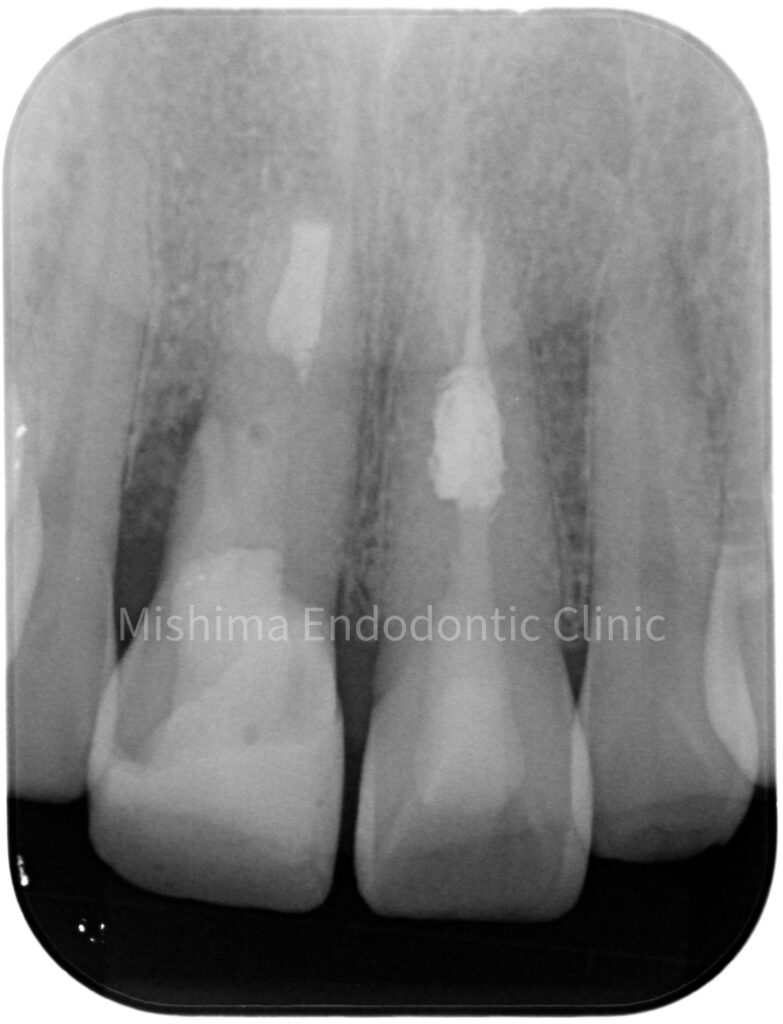

術前

| 治療内容 | 6年前にサバイバルゲームでBB弾が歯に当たり、歯が欠けた。 歯髄診査では、11,21ともにEPT+、Cold+。11は侵襲性歯頚部吸収、21は内部の炎症性吸収と診断。また、11にはパーフォレーションも認めた。 21は根管治療、ダイレクトボンディングにて対応。 11は、歯冠部の審美に対してはダイレクトボンディングにて対応。 まず侵襲性歯頚部吸収による吸収部を粘膜剥離しバイオデンティンにて外部より封鎖。後日、パーフォレーション部をバイオデンティンにて根管内部よりリペア。歯髄は正常と診断したが、予防的に根管治療を行うこととした。歯冠部からのアクセスが困難だったため、逆根管治療(歯根端切除術)にて対応。 |